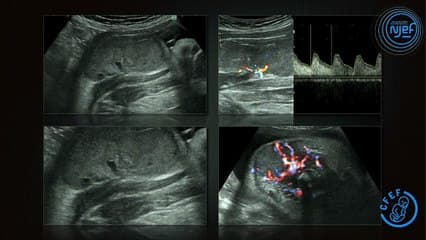

Deux ans après, les techniques ont fait des progrès : échographie haute fréquence, cartographie doppler, IRM, description des implications sur tout le tube digestif avec exemples sure des pathologies courantes, atrésie de l’œsophage, du grêles, etc..